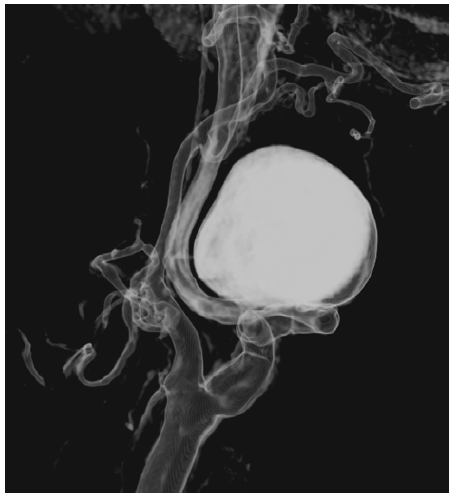

Computed tomography angiography (CTA) showed a saccular aneurysm of the left internal carotid artery with a significant tortuosity (Figures 1 and 2).

Figure 2 Preoperative computed tomography angiography reconstruction of the saccular internal carotid aneurysm

The aneurysm measured 28mm x 30mm and was located near the base of the skull, arising 30mm after the carotid bifurcation. The CTA had also highlighted significant tortuosity of the contralateral ICA but without aneurysmal degeneration. Because of the tortuosity of the ICA, not technically feasible for endovascular repair due to the diameter and absence of optimal distal neck, the volume of the aneurysm, and mass-related symptoms, open repair was preferred to endovascular exclusion as the latter (by excluding the ECAA with a covered stent or embolizing the aneurysm with coil spirals); would not address the mass effect and potential development of permanent cranial nerve injury.